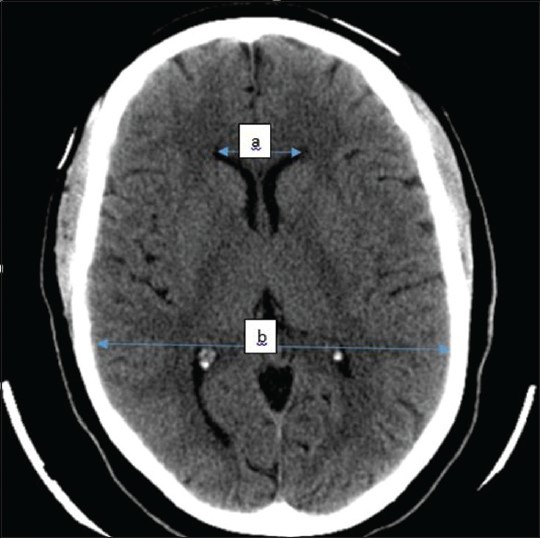

Ethical consideration does not permit that healthy individuals with no clinical symptoms be subjected to ionizing radiation. Therefore, CT scans of neurologic patients which were reported to be normal were reviewed for this study. Being a retrospective study, patient consent was not required however; this research was approved by the ethics committee of Ahmadu Bello University Teaching Hospital. Scan reports of 492 patients that were reported as normal were reviewed independently alongside their images by two radiologists. However, a total of 488 patients were finally selected and were analyzed for the study. They consisted of 319 males and 169 females and ranged between 18 and 84 years old. CT images were obtained from the local database of the CT machine and back up compact discs from the CT archives. All patients had two-phase examination (pre and post contrast studies) of the brain using the department's Siemens CT scanner (Sigma Excite HD) at 2.5 mm slice thickness at the skull base then 5 mm to the vertex. The images were viewed on the computer monitor using a meter rule with which the following measurements were made as seen in Figure 1.

Figure 1.

Illustrative axial CT section of one of the selected patients showing how measurements were taken Total anterior horn width (TAHW) =a Maximum intracranial diameter (MICD) =b

Total Anterior horn width (TAHW): a

Maximum intracranial diameter (MICD): b